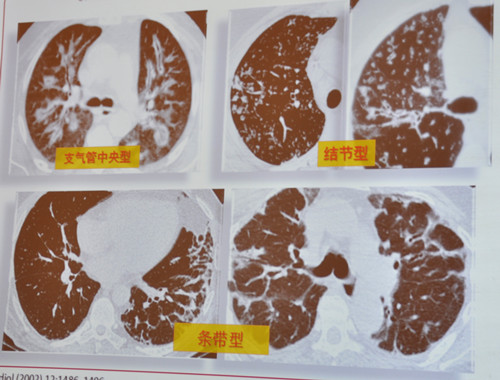

COP的影像表现